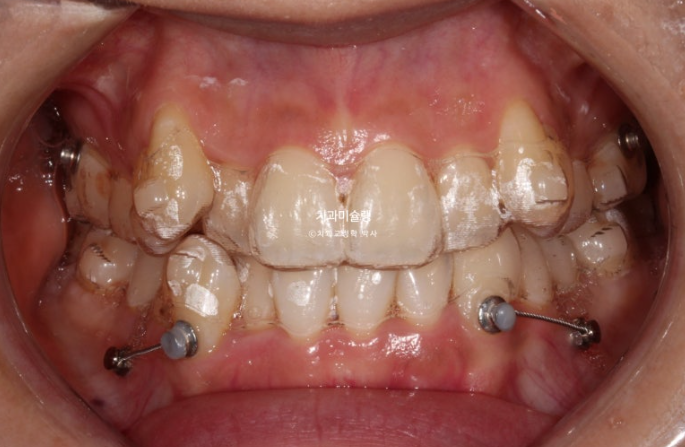

23.08

어금니 후방이동을 위한 교정용 나사도 심고

사랑니는 초반부터 장치가 잘 맞지 않아 잘라낸 후 치아에 걸어놓는 고무로 회전을 도모합니다.

첫세트 장치는 70개가 나왔습니다만 재제작은 50단계에 들어갔습니다

24년 9월까지 50개 장치 모두 낀 후 모습입니다.